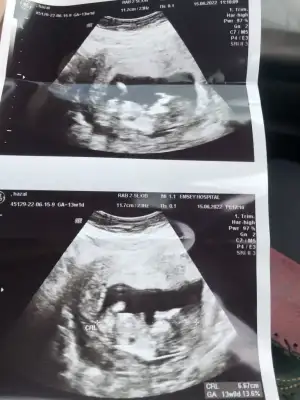

paşa gibiEki Görüntüle 3084920 11+6 Karından ultrason![]()